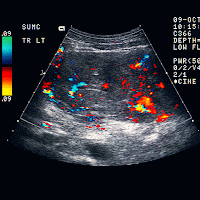

HISTORY: 59-year-old male with hepatitis-B; rule out hepatoma.

lobe of the liver demonstrating a focal hepatic mass that is

characterized by peripheral hypoechogenicity and central areas of

increased echogenicity.  In addition, Image 3 demonstrates a small

echogenic focus in the right lobe.

lobe mass.  Color Doppler Images 5-7 demonstrate increased flow within

the left lobe mass.

DIAGNOSIS: Left lobe hepatoma in a patient with known hepatitis-B.